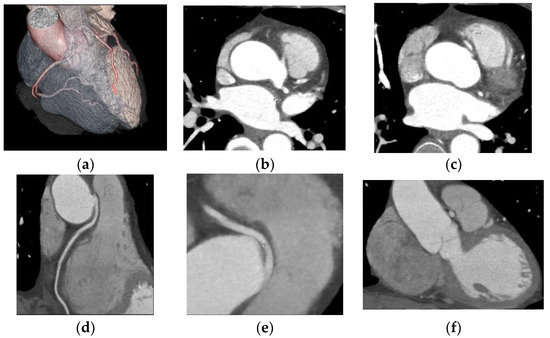

Two cases of separate origins of LAD and LCX arising directly from the left coronary sinus were found, as illustrated in Figure 3.

Two cases of separate origins of the LAD and LCX directly from the left coronary sinus were detected. Separate origins of LAD and LCX from the left coronary sinus is considered a benign variant, but some CAA classifications include it. It is considered a common CAA with a frequency between 0.41% and 0.67% [5,24].

Figure 3. Separate origins of the left anterior descending artery and circumflex artery from the left anterior coronary sinus. CCTA Volume rendered 3D images of the vascular tree anatomy, showing the LAD and LCX arise directly from the left coronary sinus. RCA with normal origin from the right coronary sinus and normal course.